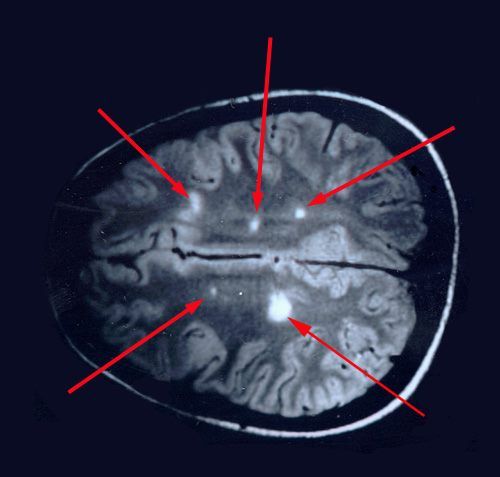

Особенности МРТ диагностики рассеянного склероза с контрастом и без него

Разрушение оболочки нервного волокна (демиелинизация) на начальной стадии размерами 1-5 мм не определяется при бесконтрастном сканировании.

Рассеянный склероз на МРТ без контраста – что показывает:

- Слияние очагов между собой приводит к увеличению демиелинизирующих зон. Такие дефекты можно отследить на томограммах;

- Паравентрикулярное расположение бляшек;

- Выраженность воспалительного процесса.